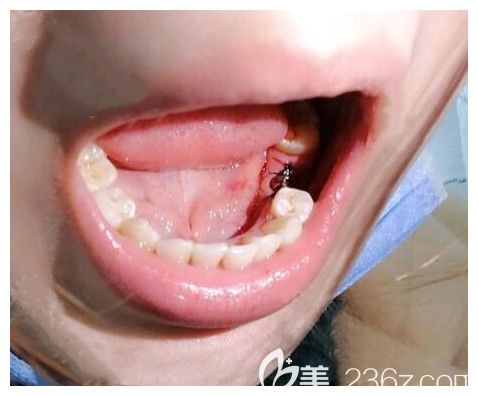

種好種植體的照片▼

種好牙根后先戴的是臨時牙冠,沒有感覺特別的不舒服,就是牙齦稍微有一點(diǎn)點(diǎn)腫、嘴巴內(nèi)有輕微的異物感,醫(yī)生說這都很正常。大概需要等3個月左右,讓種植體和自己的頜骨長到一起后再安裝上面的牙冠。